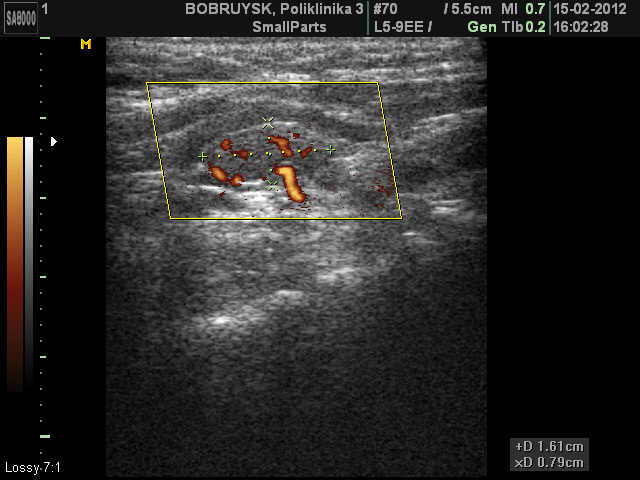

Вот такой ультразвуковой случай образования в проекции щитовидной железы.

Пациентка 66 лет. Жалоб не предъявляет

Стоит на учете у эндокринолога, диагноз не помнит, но говорит узел какой то года три назад, пунктировали, но результатов не знает и не помнит.

ADENOMA_5.JPG

ADENOMA_11.JPG

Первое впечатление - ХАИТ, псевдоузловая форма.

Я конечно же не "свадебщик", по этому в данном случае, рассматриваю вариант с аденомой паращитовидной железы. Хотя структура самой щитовидной железы, которая мной отражена не достаточно хорошо в ролике, действительно похожа на АИТ.

рассматриваю вариант с аденомой паращитовидной железы.

Возможно.

Но доказать это с помощью только УЗИ сложно, если не невозможно.

Согласен с вами, правда это же относится и к "ХАИТ, псевдоузловая форма"

Пациентке в заключении рекомендовал пункцию, попробую проследить за этим случаем.